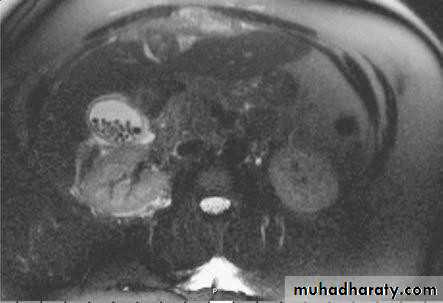

• MRCP

• Magnetic resonance cholangio- pancreatography crosssectional

• image demonstrating a hilar mass (thick• arrow) and gallstones (thin arrow)